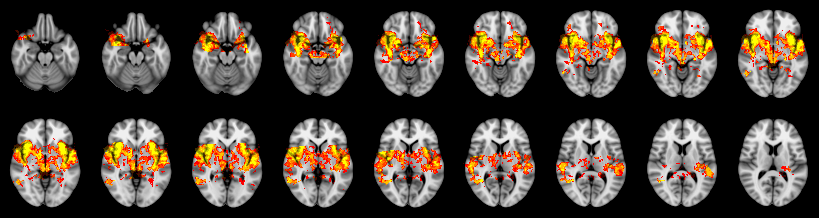

Combined

Tippett:

Fisher:

Stouffer:

Edgington:

Mudholkar–George: